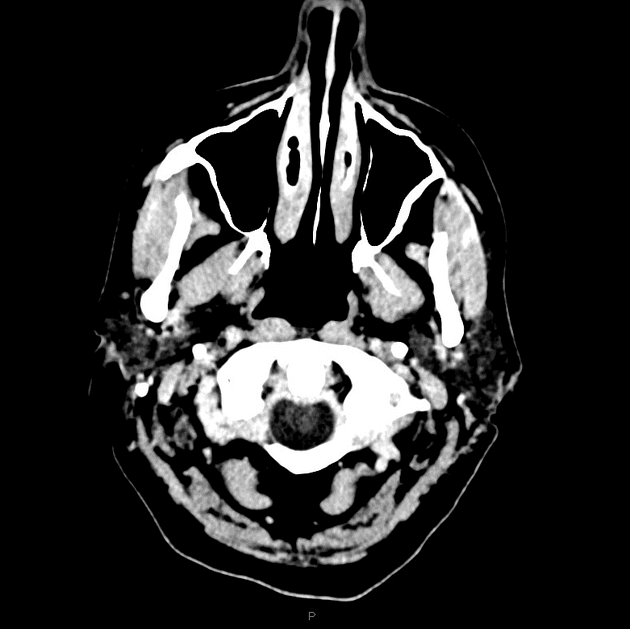

Một hình ảnh duy nhất từ chụp CT không tiêm thuốc cản quang cho thấy tổn thương dạng vòng tăng tỷ trọng (hyperdense) ở vùng ngoại vi, trung tâm giảm tỷ trọng, xung quanh có phù (oedema).

Khối ở thùy đỉnh (parietal lobe) tăng quang ở viền, trung tâm không tăng quang, kèm theo phù vận mạch (vasogenic oedema) lan tỏa rộng xung quanh. Vòng tăng quang (enhancing rim) có hạn chế khuếch tán (restricted diffusion).

Điểm chính cần lưu ý trong ca lâm sàng này là ở các bệnh nhân suy giảm miễn dịch, ung thư hạch hệ thần kinh trung ương (CNS lymphoma) có thể biểu hiện hình ảnh đa dạng, và thường có vùng trung tâm không tăng quang.

- "Ở bệnh nhân suy giảm miễn dịch, ung thư hạch hệ thần kinh trung ương nguyên phát thường biểu hiện là khối tăng quang ở viền, trung tâm không tăng quang và hạn chế khuếch tán tại vòng tăng quang."